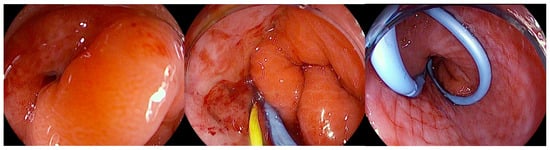

5.1.3. Endoscopic Internal Drainage

In patients who develop leaks or fistulas following bariatric surgery, it is increasingly recognized that techniques aimed at directly closing the defect do not always represent the optimal strategy, particularly once the lesion has become chronic and epithelialized. In such cases, promoting internal drainage by maintaining the fistulous tract open may be more effective [91]. This approach is based on the principle that, when intragastric pressure is lower than the pressure within the perigastric collection, fluid preferentially drains into the stomach, leading to progressive emptying and eventual collapse of the cavity [75]. Clinical success is therefore better assessed by dietary tolerance and reduction in the size of the perigastric collection rather than by the mere narrowing of the fistulous orifice. For endoscopic internal drainage (EID) to be effective as a stand-alone therapeutic strategy, however, certain conditions must be absent, including disorganized collections, distal stenosis resulting in elevated intragastric pressure, or the presence of a gastropleural fistula [92]. The concomitant use of percutaneous drains must also be carefully managed: continuous drainage lowers intracavitary pressure and prevents effective internal drainage into the gastric lumen. For this reason, such drains should remain clamped and only be opened during scheduled lavage procedures. Several endoscopic approaches can facilitate internal drainage, including the placement of short, small-caliber double-pigtail stents (DPSs) and endoscopic vacuum therapy (EVT). Among these, DPS is the most commonly adopted technique, with routine exchanges performed every 2–4 weeks until the perigastric cavity has nearly resolved while EVT applies continuous negative pressure to promote cavity closure [93]. Ultimately, the choice of technique should be individualized, and in many cases require a multimodal and sequential approach. The goal is not necessarily immediate fistula closure but rather the restoration of a favorable pressure gradient that facilitates gradual resolution of the perigastric cavity. DPS are plastic devices (most commonly made of polyethylene or polyurethane) specifically designed to facilitate internal drainage within the gastrointestinal tract. Their tubular structure is characterized by bilaterally curled ends (“pigtails”), which act as anchors to minimize the risk of migration both into the gastrointestinal lumen and into the drained cavity. They are available in a wide range of calibers, typically between 5 and 10 Fr, and lengths from 5 to 18 cm, with some models incorporating multiple lateral side holes to enhance drainage capacity, as well as radiopaque markers to ensure accurate positioning under fluoroscopic guidance. Deployment is generally performed over a 0.035-inch guidewire using radiopaque pusher catheters, which facilitate advancement even through tortuous tracts [94] (Figure 6).

Figure 6.

Endoscopic view of a gastric fistula after sleeve gastrectomy communicating with a perigastric cavity, showing the transfistulous endoscopic placement of a 0.035 Fr radiopaque guidewire followed by deployment of a double-pigtail plastic stent. The copyright of this figure belongs to the authors.